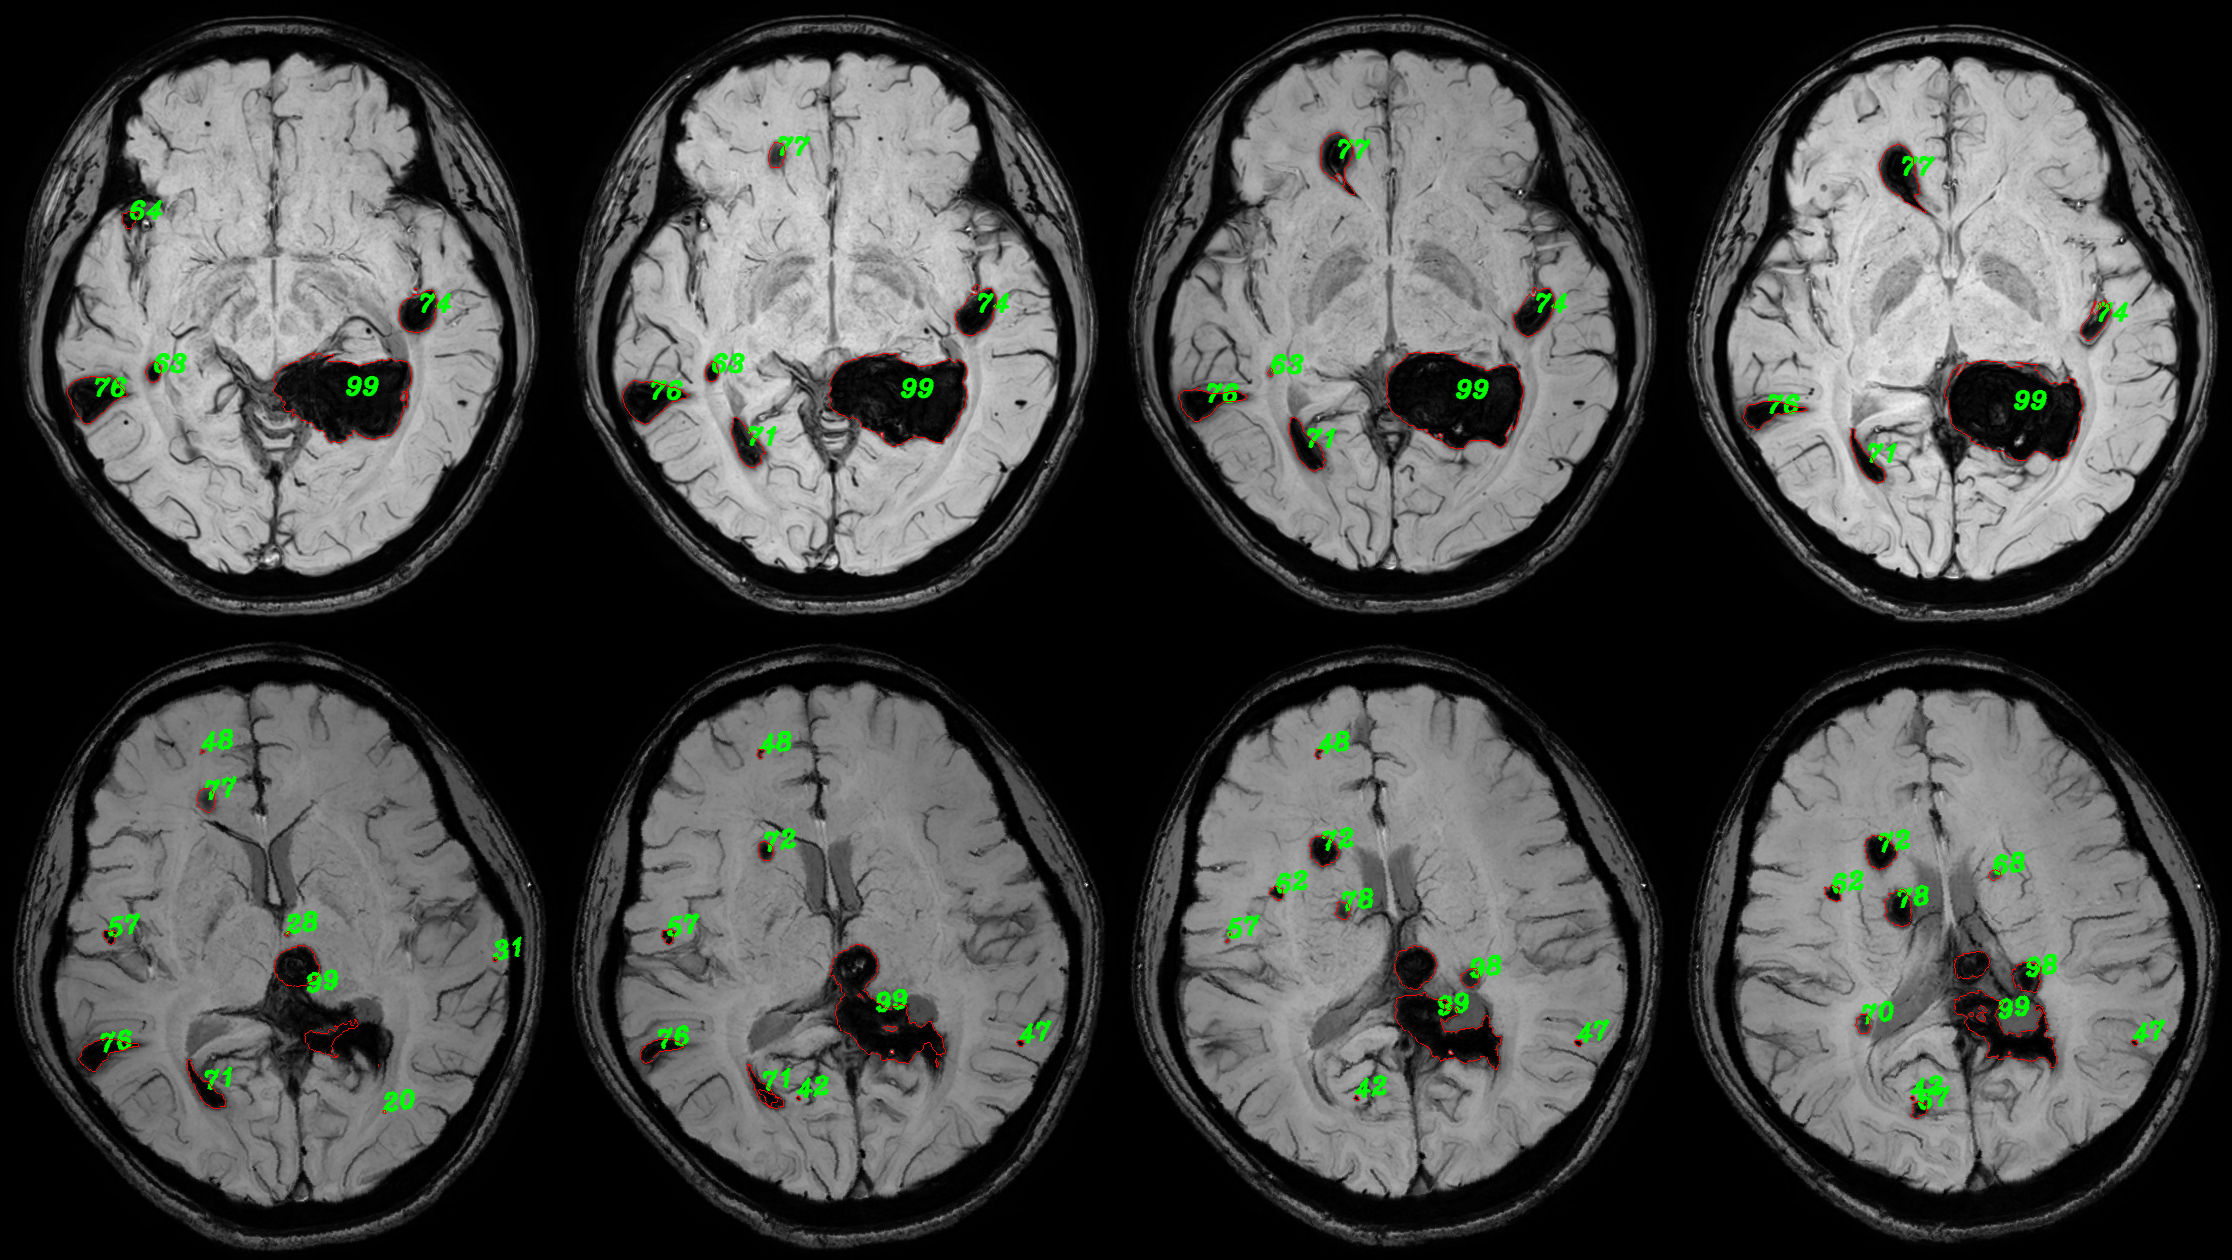

Refer to caption

Figure 7: Quantitative analysis visualization collage. This example consists of consecutive images from four planes of cranial MRI SWI sequences for two inspections of one patient. Numerals correspond to the indexes of the respective 3D lesion bodies. The red contour represents the visualization of the contours of the lesion segmentation predicted masks.

4.3 Quantitative statistics results

In the FCCM lesion quantitative statistics module, 2D segmentation results of lesions were first acquired, and then a 3D segmentation mask was synthesized for quantitative statistics. The statistical information included the number and volume of lesions, and a comparative statistics of lesions between two examinations of the same patient was conducted. The quantitative statistical results of a case were presented to demonstrate the effectiveness of the proposed lesion quantitative statistical module. Figure 7 showed the results of quantitative analysis visualization, where the numbering of each lesion and the contour of the lesion segmentation mask were plotted on the original FCCM image. The visualization collages of the entire volumes were shown in Figure 2 and Figure 3 in the Appendix A. The numberings and corresponding volume/volume pairs of lesions with a volume greater than 100 were presented in Table 3. The shaded areas depicted multiple lesions in the follow-up inspection that matched the same lesion in the previous inspection. This was mainly due to the irregular shape of the lesions, with discontinuities appearing in different planes. It manifested as a large lesion with several smaller lesions, resulting in a many-to-one situation. Figure 7 could help doctors more intuitively compare the lesion and its segmentation mask, assist in distinguishing the lesion area, and combined with Table 3 to conduct quantitative analysis on the lesion, making a more objective diagnosis of the condition.

In addition, further processing of quantitative statistical results could also help doctors have a better grasp of the patient’s overall condition progression. For lesions with a volume greater than 100 in the two examination results, the volume broken line diagrams of unsuccessfully matched and successfully matched lesions were plotted in ascending order, as shown in Figure 8. By comparing the volume curves of lesions from two examinations, we could intuitively find that the volume of one lesion exhibited a significant reduction during the follow-up examination. Analysis in conjunction with Figure 7 (see Figure 2 and Figure 3 in the Appendix A for details) indicated that this reduction was attributed to surgical intervention in the lesion area. No significant changes were observed in the overall size of other lesions. Simultaneously, a categorized statistical analysis of lesion volumes in the follow-up inspection was performed, as presented in Table 4. Based on these results, physicians could gain a clearer understanding of the quantity of severe brain lesions in patients than without using the quantitative statistical method, enabling better clinical decision-making.

5.3 Effects of quantitative statistical module

Based on the experimental results, we analyze and discuss the effects of the quantitative statistical module. The statistical analysis of FCCM lesion volume and quantity plays a significant role in assisting clinical diagnosis and screening smaller lesions for early. However, currently widely adopted manual measurement methods often come with high time and resource costs. Additionally, different operators may interpret and standardize measurement results differently, leading to increased subjectivity and variability in measurements, inevitably introducing measurement errors. Therefore, a quantitative analysis of 3D masks synthesized based on FCCM segmentation results is performed. We quantify the volume by counting the number of pixels occupied by the lesions, calculate the number of lesions based on the segmented target regions, and establish a visualization framework. The quantitative analysis visualization collage presented in Figure 7 (see Figure 2 and Figure 3 in Appendix A for details) enables doctors to quickly diagnose lesion areas and assess the accuracy of the predicted masks based on the original image. Lesion numbering assists doctors in locating corresponding lesion volume information, particularly the volume information for successfully matched lesions. Combining the overall trend of lesion volume changes between two examinations, as shown in Figure 8, provides better diagnostic insights into the patient’s condition and disease progression and offers a quantitative assessment method for drug efficacy.